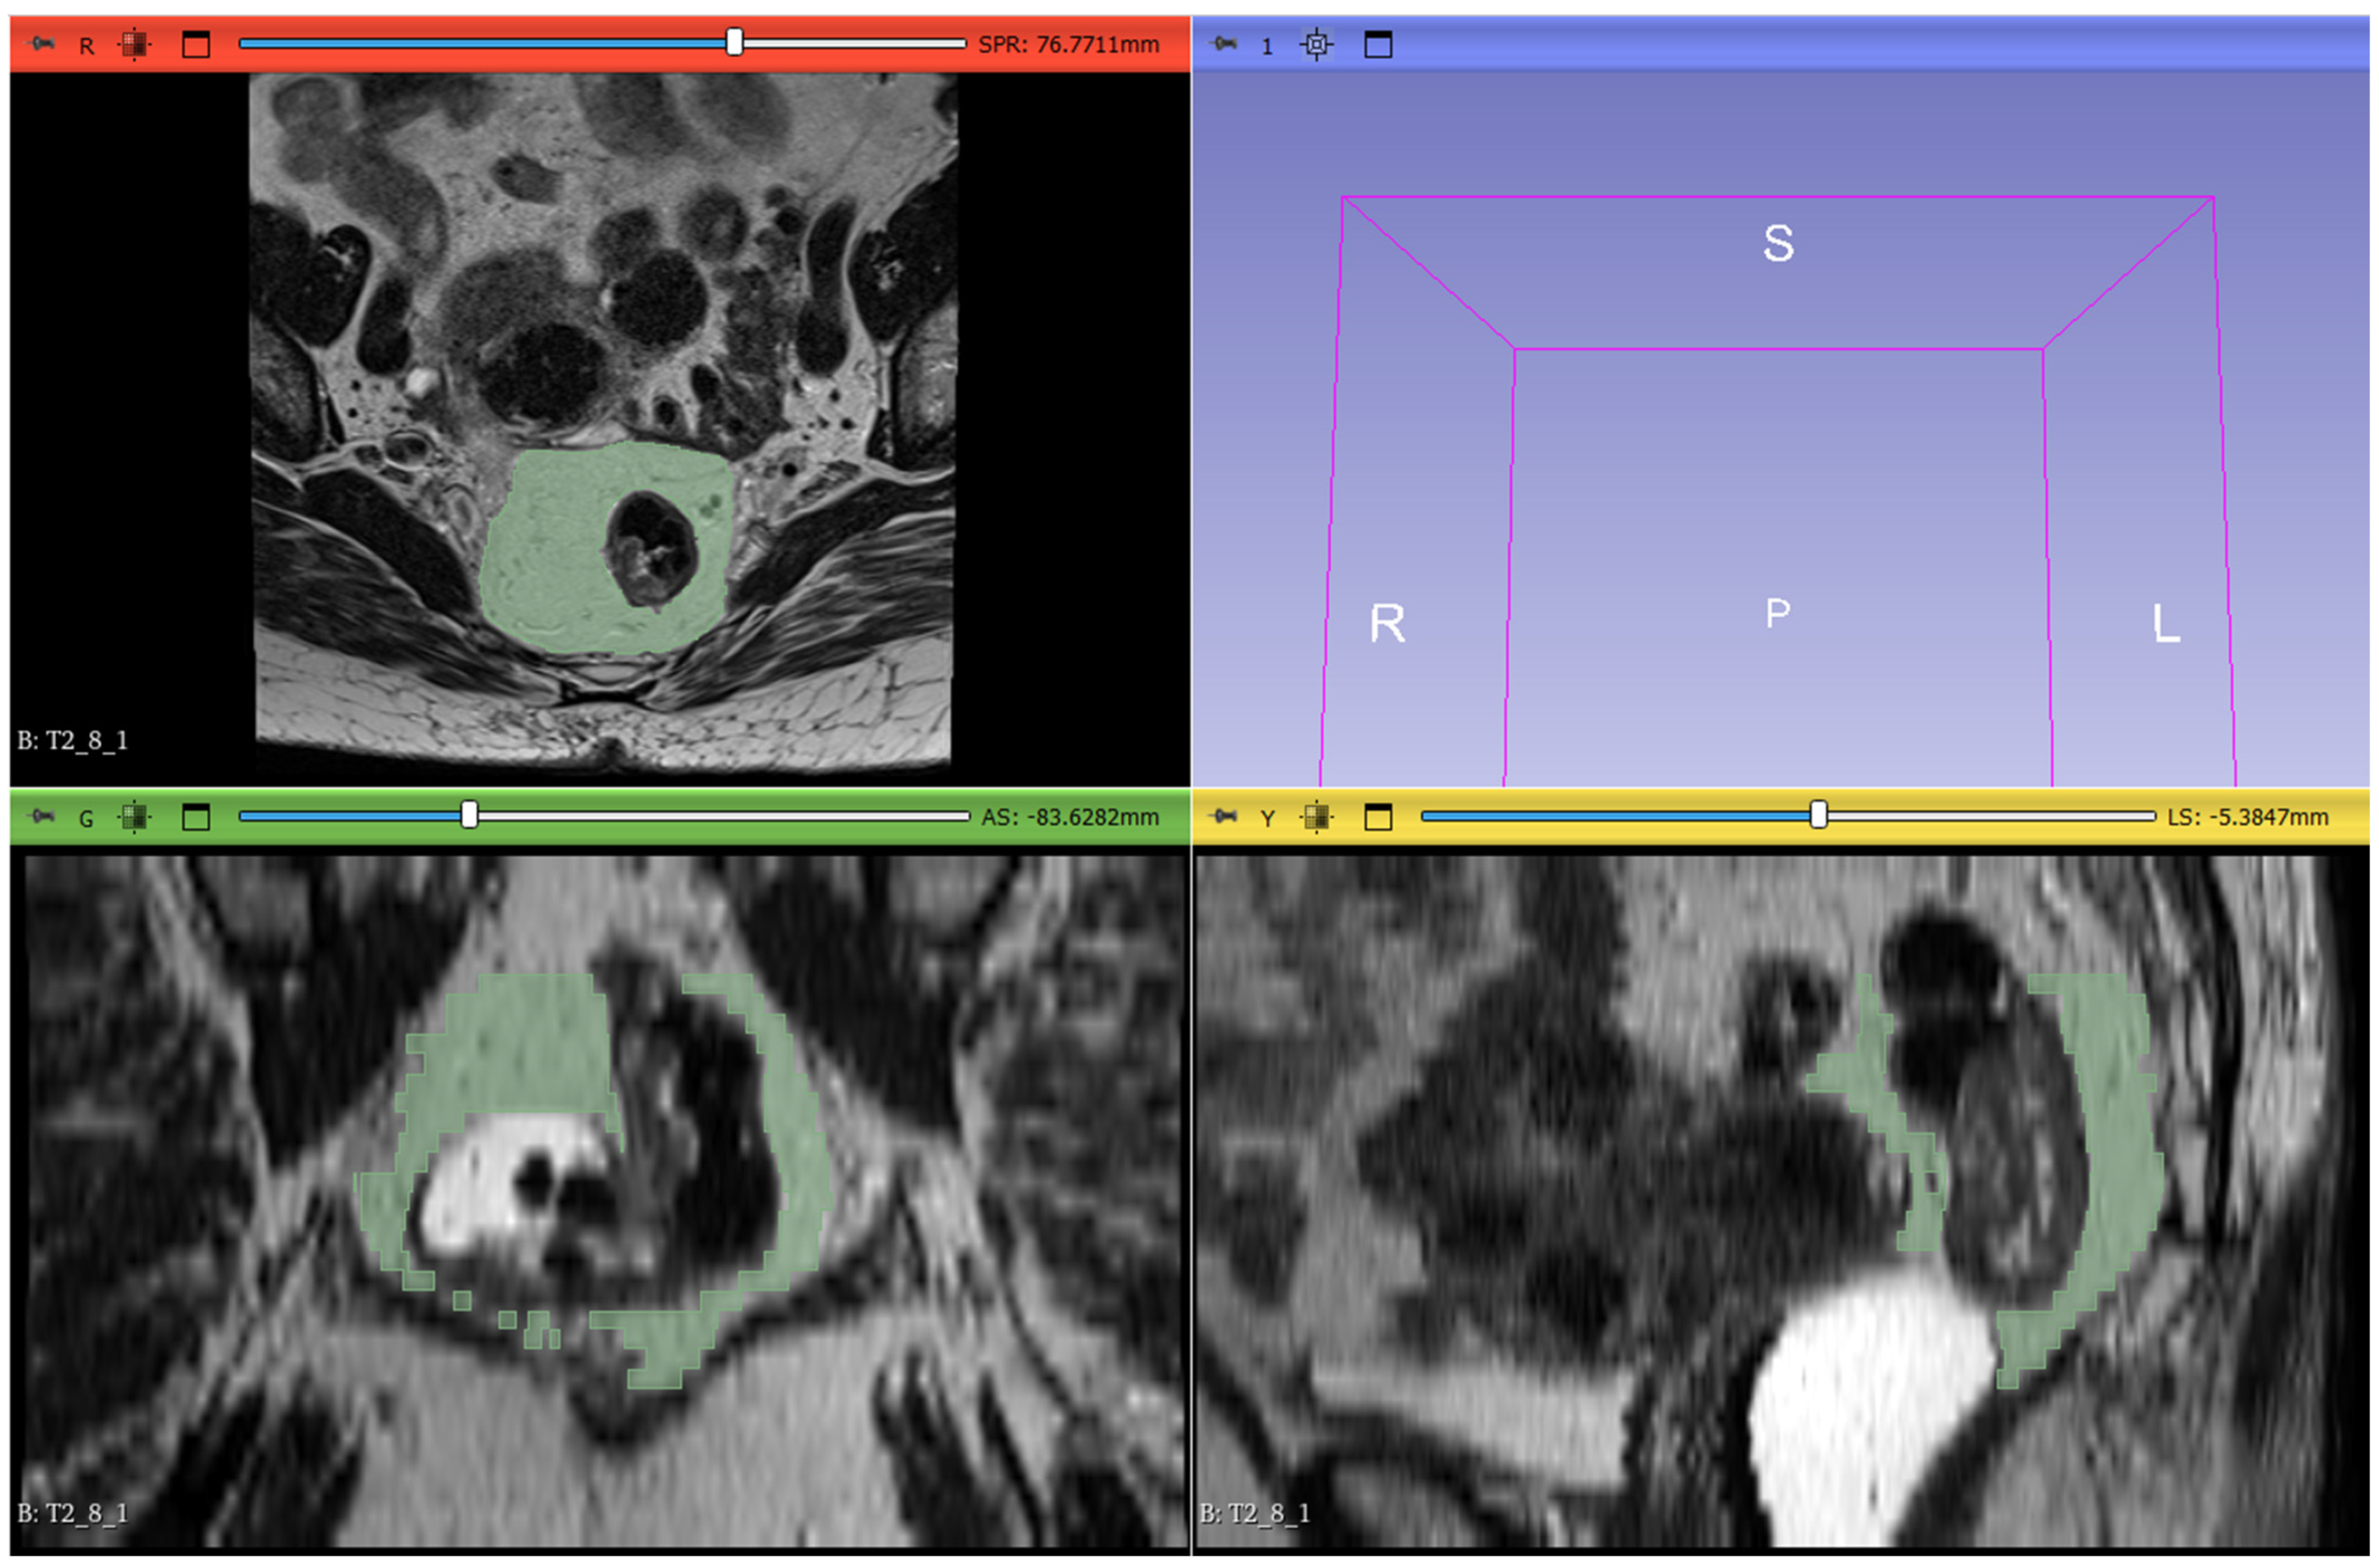

2.5. Radiomic Workflow

The radiomic workflow included lesion segmentation, feature extraction, and feature selection. T2-weighted images from the staging MRI were imported into 3D Slicer software (version 5.6.1) for segmentation. Radiologists manually delineated the mesorectal fat on all slices, defining the region of interest (ROI). The proximal boundary was defined at the point where the anterior peritoneal reflection attaches to the rectal wall (visible as a V-shaped structure on the axial plane), and the distal boundary was set at the last visible portion of mesorectal fat above the intersphincteric plane. The segmentation excluded the rectum, the tumor, any tumor deposits within the mesorectal fat, pathological lymph nodes, and mesorectal vessels invaded by the disease (Figure 2).

Figure 2. The image-processing software 3DSlicer was used to manually delineate ROIs along the lesion margins on all slices containing the tumor in the MRI T2w sequences (red, green, and yellow squares), as illustrated in the figure. The volumetric 3D reconstruction of the tumor is displayed in the upper—right quadrant (light blue square).